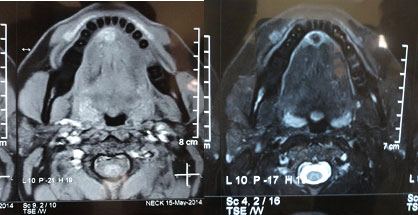

Diascopy test was not done because of anatomy and FNAC did not yield any aspirate. Intraoral periapical radiograph with respect to mandibular anterior teeth and mandibular topographical occlusal view showed no abnormality [Table/Fig-2]. MRI revealed patchy area of signal abnormality in floor of mouth, infero-medial to attachment of geniohyoid muscle. Mildly hypointense on T1 and T2 image was appreciated with an impression of malignancy from minor salivary gland [Table/Fig-3]. Mild diffuse restriction was noted on Diffuse weighted image (DWI). Complete surgical profile was advised in which no abnormality was detected. Correlating clinical, radiographic and MRI findings, odontogenic lesion was ruled out and working diagnosis of minor salivary gland tumour was arrived. Excisional biopsy of the lesion was performed under local anaesthesia [Table/Fig-4] and the specimen was subjected to histopathological examination.

T1 & T2 weighted images showing- iso to hyperintense area in anterior floor of the mouth